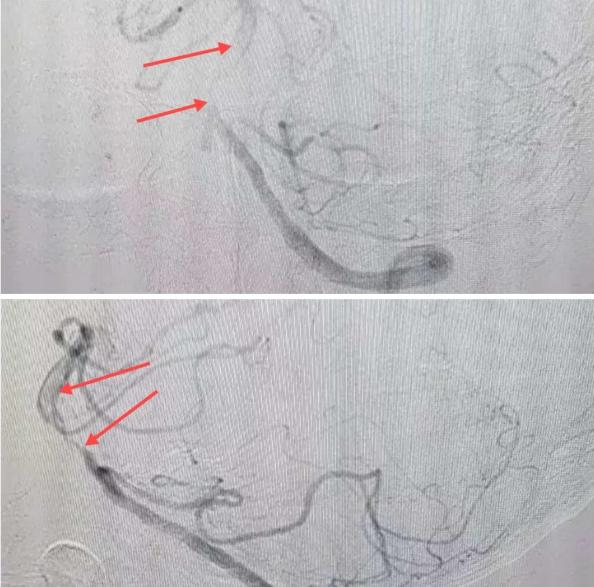

在經(jīng)造影后,主刀醫(yī)生腦一科副主任楊慶堂發(fā)現(xiàn)患者基底動脈下段重度狹窄且狹窄段以遠有大負荷血栓,其狹窄處考慮為動脈夾層,手術(shù)難度及風險較大。楊慶堂副主任在彭壯副主任醫(yī)師的協(xié)助下運用spaceman(太空人)技術(shù),中間導(dǎo)管抵近血栓抽吸配合支架拉栓,成功開通血管。再次造影可見基底動脈管腔明顯增寬,遠端血管顯影良好,且等待20分鐘后造影仍顯示血流通暢。楊慶堂副主任考慮到本次手術(shù)時間不宜過長,現(xiàn)患者基底動脈及分支前向血流維持良好,給予其抗栓藥物應(yīng)用后結(jié)束手術(shù),并建議患者3個月后復(fù)查造影,明確其基底動脈夾層情況。

造影可見血管夾層和大量血栓形成